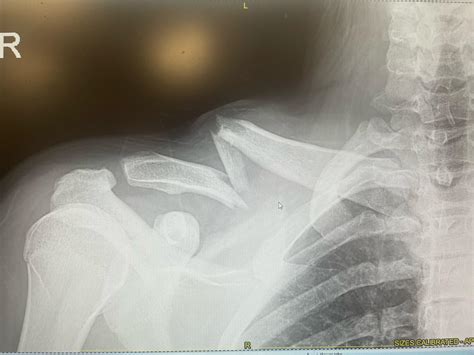

Diagnosing a Collarbone Break Bump

If you suspect a collarbone break bump, it is important to seek medical attention for a proper diagnosis. The diagnostic process typically involves:

• Physical Examination: A healthcare provider will examine the shoulder and collarbone area, checking for tenderness, swelling, and deformity.

• X-Rays: X-rays are the primary diagnostic tool for confirming a collarbone fracture. They provide clear images of the bone and can show the location and severity of the fracture.

• CT Scans or MRIs: In some cases, additional imaging such as CT scans or MRIs may be ordered to get a more detailed view of the fracture and surrounding tissues.